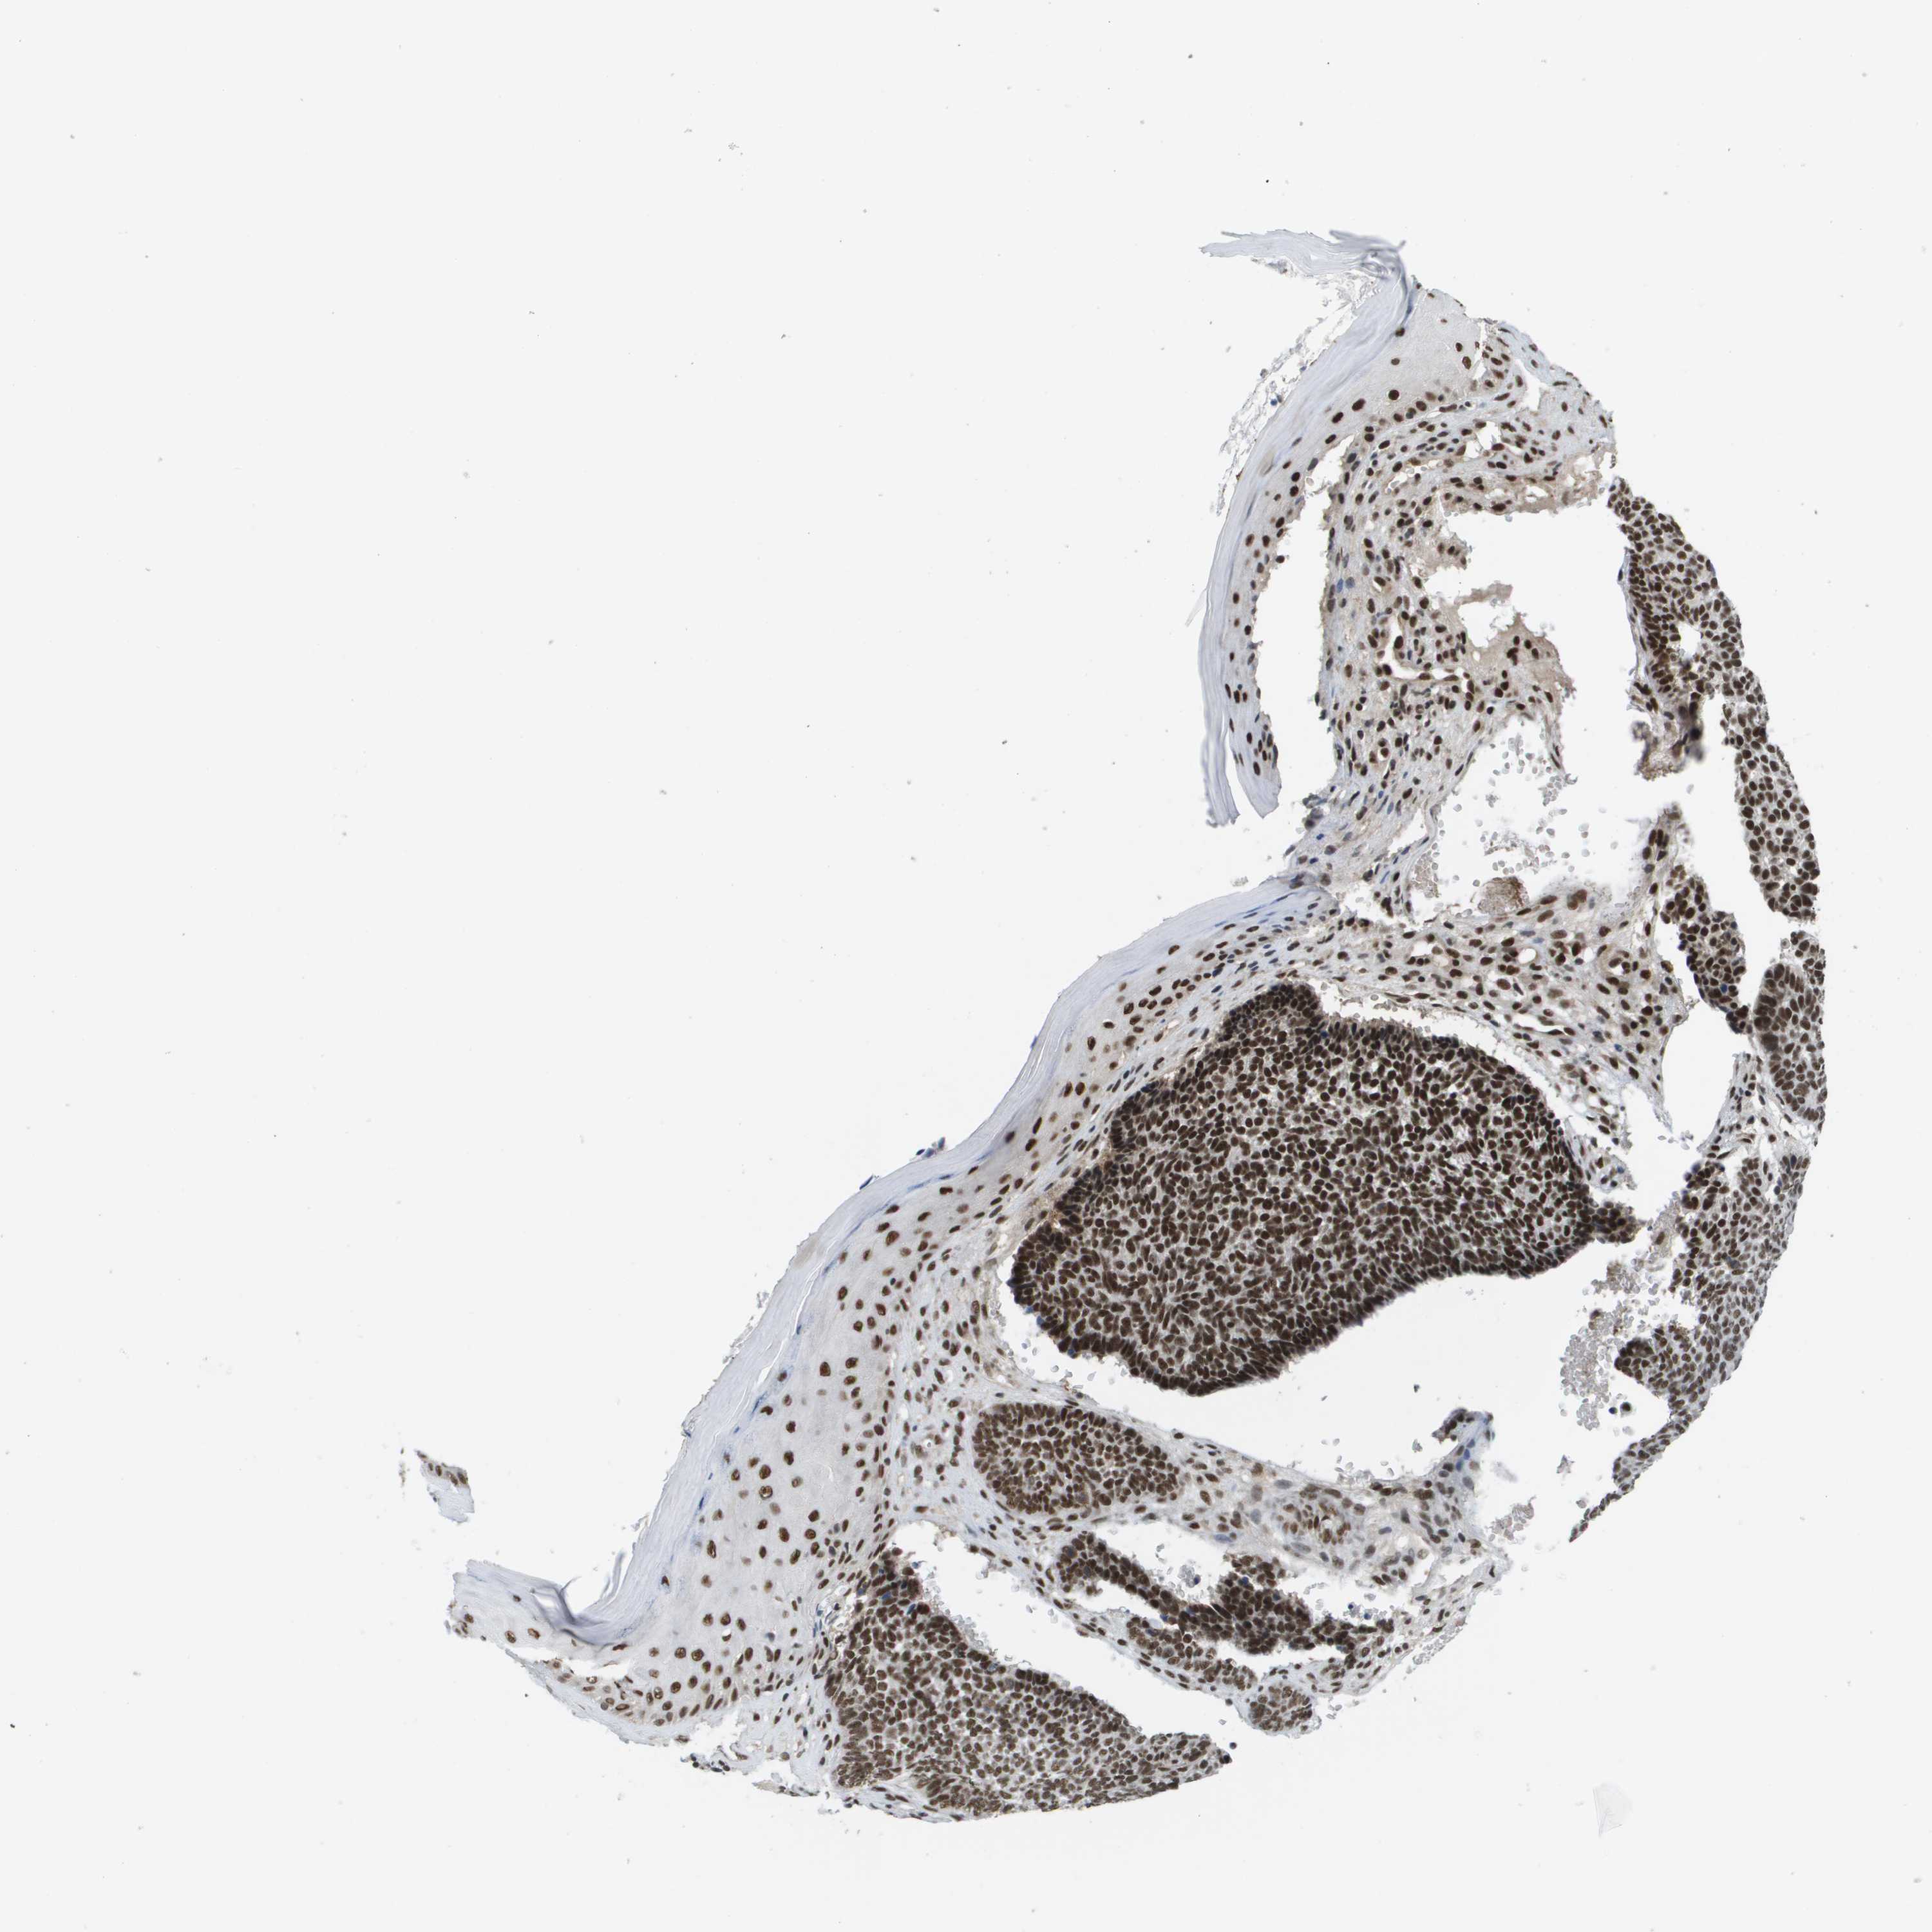

SKIN CANCER - Protein expressioni

A mouse-over function shows sample information and annotation data. Click on an image to view it in a full screen mode. Samples can be filtered based on level of antibody staining by selecting one or several of the following categories: high, medium, low and not detected. The assay and annotation is described here.

Each image is clickable and will lead to virtual microscopy that enables deeper exploration of all samples and also displays staining intensity scores, fraction scores and subcellular localization as well as patient and tissue information for each sample.

Antibody HPA019463

Staining

High

Medium

Low

Not detected

Intensity

Strong

Moderate

Weak

Negative

Quantity

>75%

75%-25%

<25%

None

Location

Nuclear

Cytoplasmic/membranous

Cytoplasmic/membranous,nuclear

Basal cell carcinoma